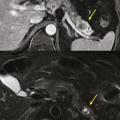

Cystadénome séreux

Il s’agit d’une tumeur kystique multiloculaire pouvant mesurer de 1 à plus de 20 cm, avec un aspect de «  cicatrice  » fibreuse centrale, parfois calcifiée (fig. 4). Ils sont plus fréquents chez les femmes (3 femmes pour 1 homme) avec un âge médian au diag­nostic autour de 60 ans. Ils sont le plus souvent de découverte fortuite ou secondaire à l’exploration de douleurs abdominales aspécifiques. Leur taille est stable dans le temps dans 60 % des cas, ou avec une croissance lente (4 mm/an). Les complications sont rares, et la dégénérescence exceptionnelle (moins de dix cas décrits dans la littérature), la surveillance n’est donc pas nécessaire. Pour les exceptionnelles lésions volumineuses (10 % de séreux macrokystiques), une chirurgie peut se discuter12 si elles sont à l’origine de symptômes invalidants.